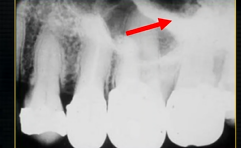

what does this anterior periapical graph show?

oval radiolucent area between the central incisors - is it Infront of the teeth (buccally?) or is it behind them? - you can’t tell radiographically

but its shape and position is compatible with the palatally positioned with the nasopalatine formaina

more posteriorly - radiopacities indicate the nasal septum and floor of the nose

dense, thin , white line in the middle of the image is the nasal septum

less dense opacity is caused by the

inferior nasal concha